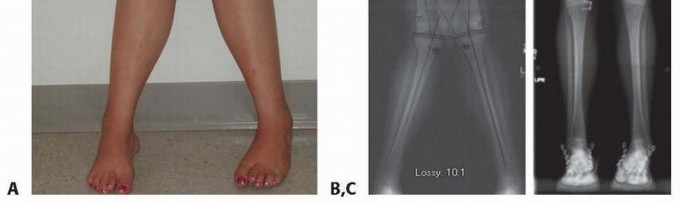

- ###

- FIG 2 • A. A 13-year-old girl with knee pain and difficulty with ambulation secondary to genu valgum. B. Standing AP radiograph of her lower extremities demonstrating bilateral genu valgum with abnormal LDFA bilaterally and an abnormal MPTA on the right tibia. She was indicated for bilateral medial distal femoral

- guided growth and right medial proximal tibia guided growth. C. Standing AP radiograph at 7 month postoperatively demonstrates normalization of her mechanical axis. (Courtesy of UW Pediatric Orthopaedics.)

- Medial distal femur or proximal tibia for genu valgum (FIG 2) Lateral distal femur or proximal tibia for genu varum (FIG 3) Anterior distal femur (FIG 4)